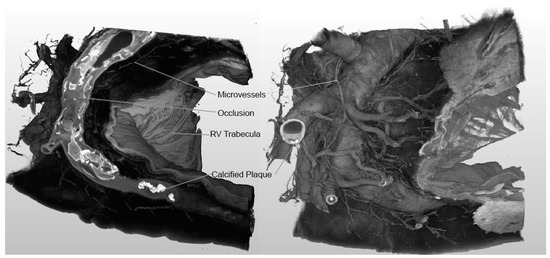

3.1. Imaging Outcomes and Generated Models

- Enabling novel explorations of the presence or absence of continuous intralesional microchannels that may present in a heart with true chronic total occlusions, including their complex and highly variable three-dimensional paths. Previous work on these anatomies has been limited to cross-sectional pathology/HE slices or rabbit animal models of the femoral artery [5].